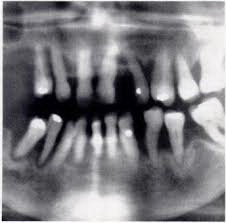

Periodontal Examination & Charting

Precision matters in periodontics.

You will learn to:

- Assist during comprehensive periodontal evaluations

- Understand probing depths and attachment loss

- Recognize bleeding indices and mobility

- Support radiographic interpretation

- Accurately document findings

Clear and accurate periodontal charting is essential for both patient care and legal protection.